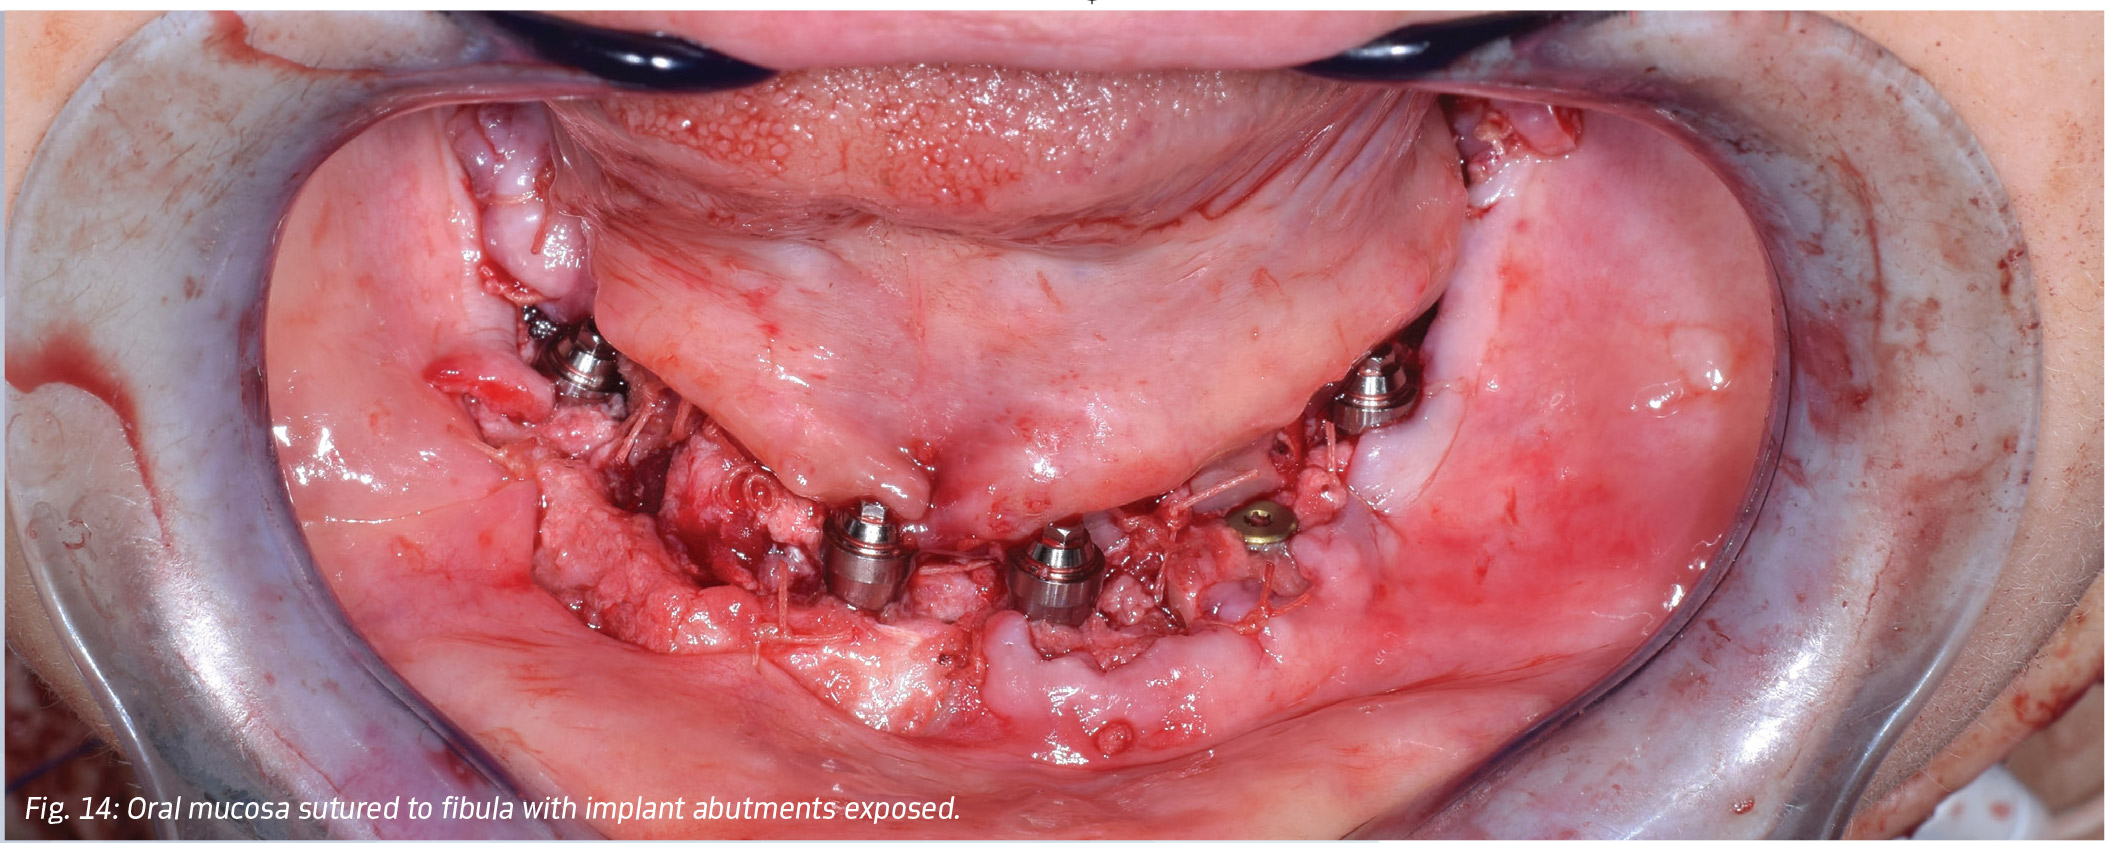

The neck was closed with 3-0 vicryl at the level of the platysma muscle, and 4-0 Prolene for skin. The oral mucosa was sutured to the fibula, with care to maintain exposure of the abutments (Fig. 14). The final hybrid prosthesis was placed and occlusion verified (Fig. 15). A postoperative CBCT scan showed the accuracy of implant placement, fixation screw placement and bone positioning possible with virtual 3-D planning (Figs. 16 and 17).

Building a MandibleFig. 14: Oral mucosa sutured to fibula with implant abutments exposed.